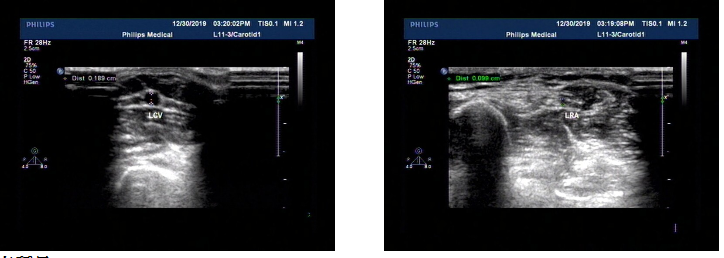

术前超声检查提示:双侧上肢血管较细小。右侧前臂桡动脉内径1.3mm,前臂头静脉内径1mm。

术前超声检查